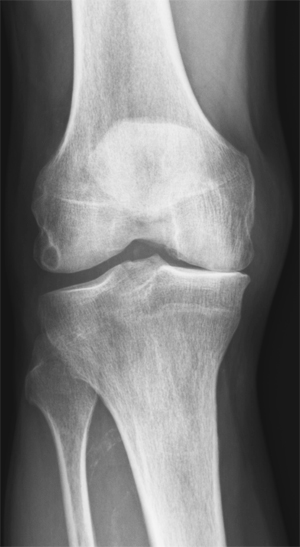

For ti år siden fikk jeg besøk av en pasient med store plager fra artrose i det ene kneet. Han hadde tatt røntgenbilde av kneet og fått vurdering av ortoped, som konkluderte med at det var så stor artrose at protese var eneste aktuelle behandling. Pasienten var fysisk svært aktiv, både på ski og med fotturer i fjellet, og var lite innstilt på proteseoperasjon. Han kjente til at jeg hadde lang erfaring med behandling av idrettsutøvere med plager fra muskler og ledd, og ba om time, selv om han ikke var en av mine ordinære pasienter.